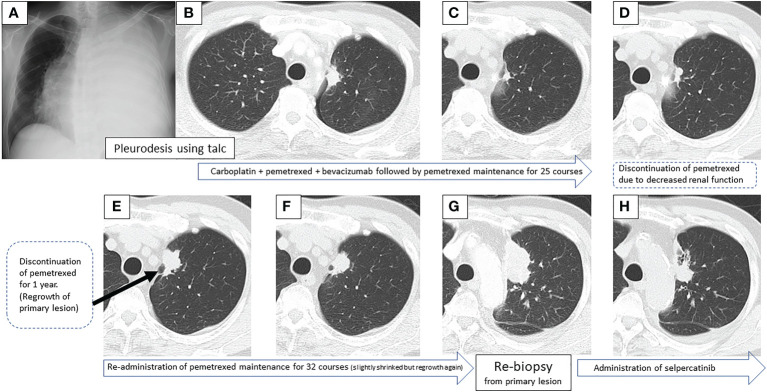

一名67歲的男性,從未吸煙,無顯著病史,因為左側(cè)大量胸腔積液(圖1A)被轉(zhuǎn)診至佳學(xué)基因腫瘤基因檢測病例交換醫(yī)院。對左側(cè)胸腔積液進行的細胞學(xué)評估顯示V級腺癌,與細胞塊病理評估一致。使用滑石粉進行胸膜固定后,肺部膨脹良好,左S1 + 2a處出現(xiàn)一顆25×17mm的結(jié)節(jié),被認(rèn)為是原發(fā)病灶(圖1B)。臨床上,他被診斷為腺癌T1cN3M1a,IVA期。初次基因突變篩查進行于七年前,使用其他機構(gòu)的進行的EGFR突變和ALK免疫組化(IHC)測試結(jié)果均為陰性。

圖1:在先進次就診到開始進行第二次治療期間,患者7年間原發(fā)病灶的順序圖像

一線治療包括卡鉑+培美曲塞+貝伐單抗,經(jīng)過4個療程后獲得近乎有效緩解(CR),但鼻出血仍然持續(xù),僅進行培美曲塞維持治療。在維持治療的25個療程中實現(xiàn)了CR(圖1C),但由于腎功能輕微惡化,治療暫時中斷。治療結(jié)束后一年,CT顯示原發(fā)病灶輕微進展(圖1D),但反復(fù)速度較慢。確認(rèn)CT反復(fù)一年后(圖1E),重新開始培美曲塞單藥治療,原發(fā)病灶和淋巴結(jié)減?。▓D1F)。然而,在進行了32個維持治療療程后,出現(xiàn)了快速的全身進展。由于原發(fā)病灶再生(圖1G)、對側(cè)肺轉(zhuǎn)移、多發(fā)性肝轉(zhuǎn)移、右側(cè)腎上腺轉(zhuǎn)移和多發(fā)性腦轉(zhuǎn)移(圖2A、B),需要調(diào)整他的治療方案。

通過支氣管鏡對原發(fā)病灶進行再活檢,細胞學(xué)評估顯示V級腺癌,組織學(xué)評估證實了這一結(jié)果。腫瘤正確用藥850基因檢測確認(rèn)患者為RET融合基因陽性,隨后于第二天給予240mg塞爾帕替尼。第13天的CT顯示與基線影像相比(圖1H),所有轉(zhuǎn)移病灶,包括腦轉(zhuǎn)移(圖2C、D),均有良好的全身反應(yīng)。由于2級肝酶升高,繼續(xù)給予劑量減少的塞爾帕替尼(每天160mg)。使用高敏感度的下一代測序(NGS)面板系統(tǒng):肺癌緊湊面板,并使用細胞學(xué)刷液進行RNA檢測,證實了融合基因KIF5B外顯子15;RET外顯子12(K15RET12)。腫瘤正確藥基因解碼基因檢測還能夠從7年前的胸腔積液細胞塊的福爾馬林固定石蠟包埋(FFPE)標(biāo)本中進一步確認(rèn)RET(圖3A、B),這些標(biāo)本在惡性細胞的形態(tài)學(xué)上與再活檢樣本相似,具有大核仁(圖3C、D)。從初始細胞塊樣本中收集到的RNA(1256ng)具有RNA整合數(shù)(RIN)值為4.8。單重PCR和NGS檢測均檢測到了K15RET12融合峰(圖3)。